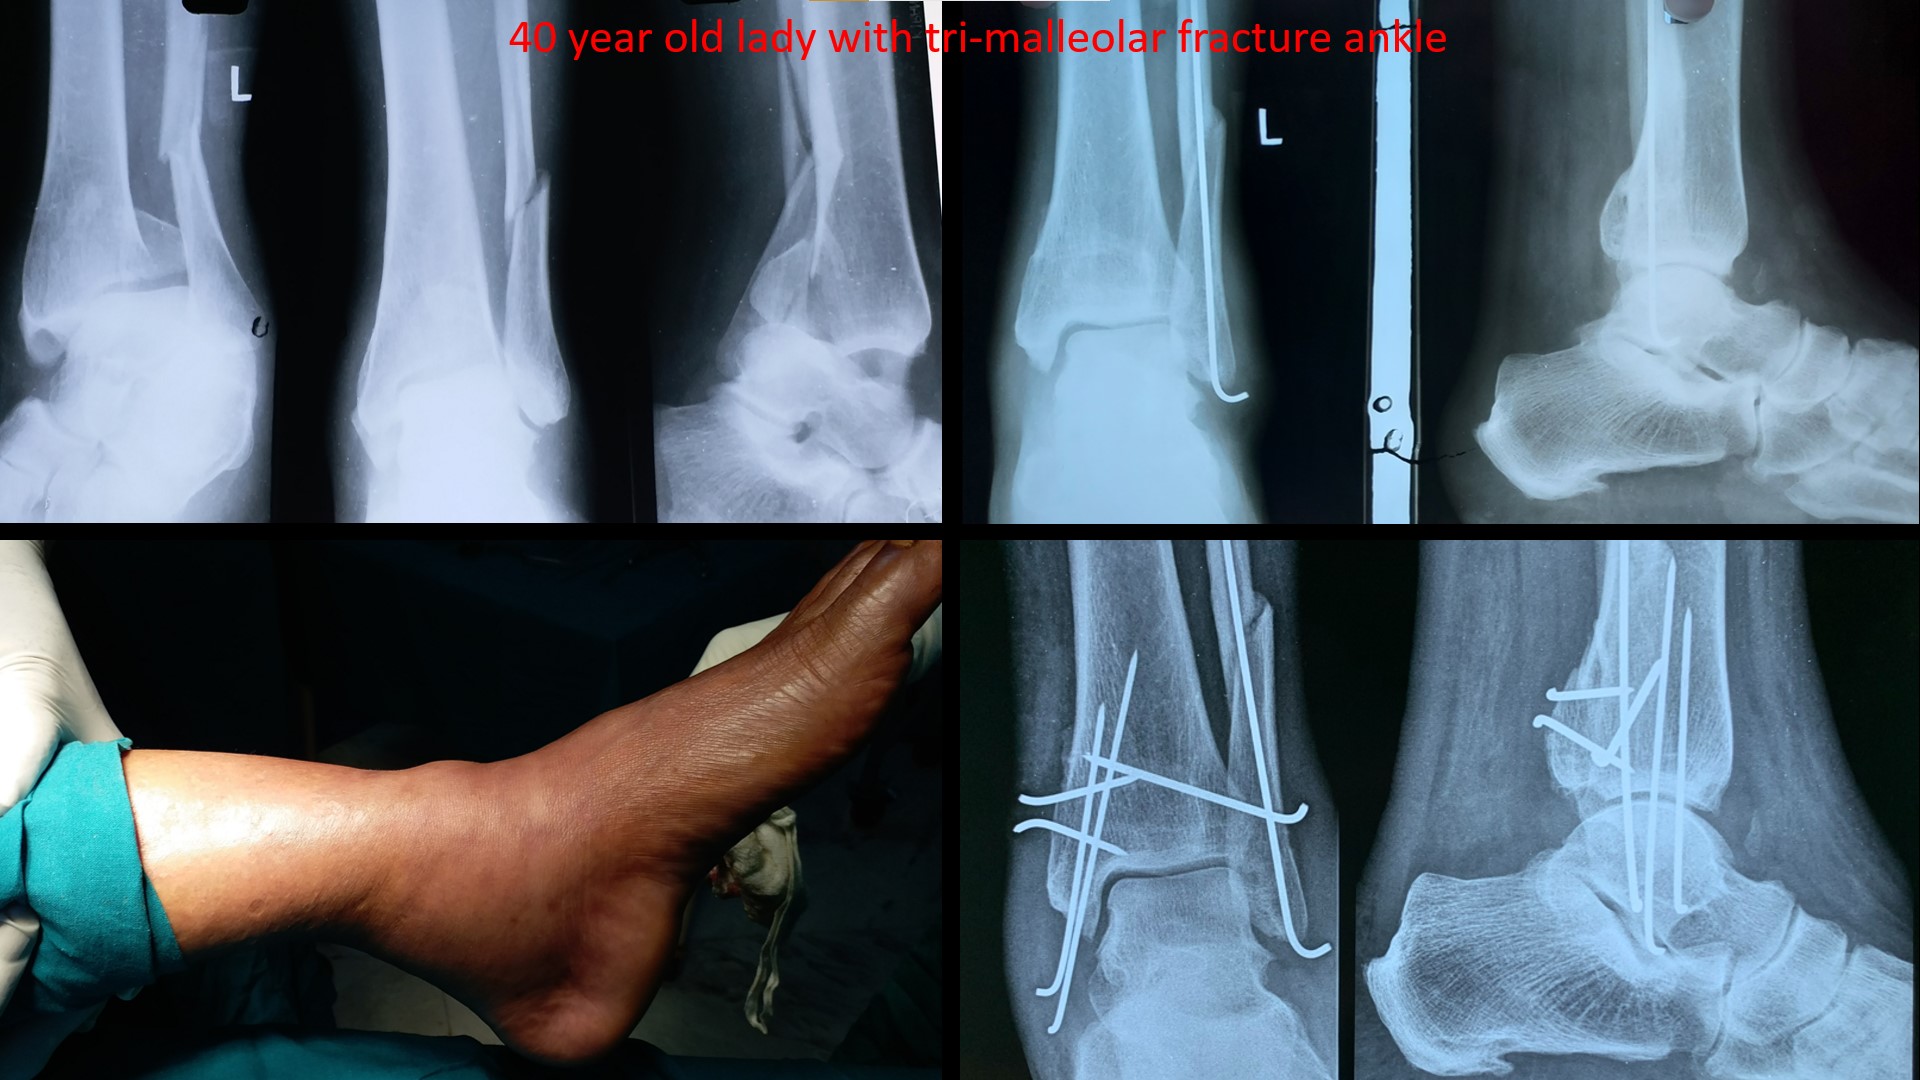

ANKLE